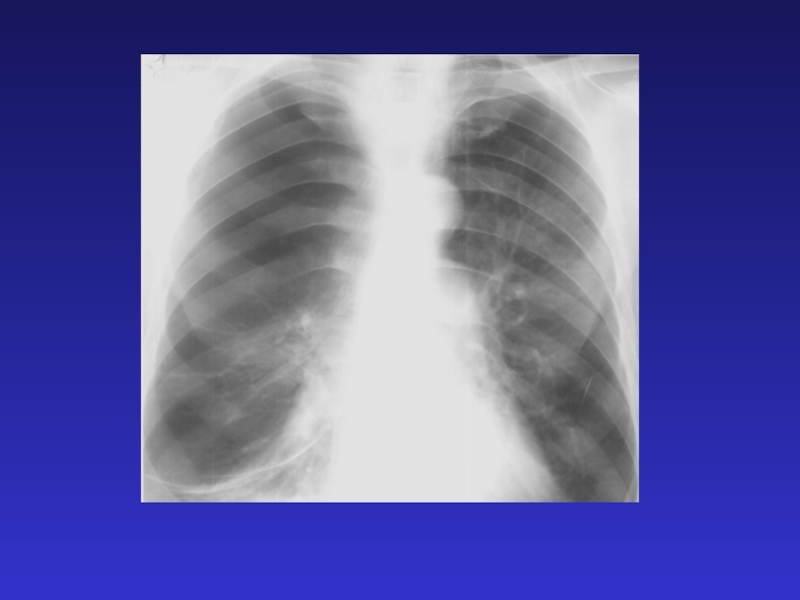

Слайд 60Эмфизема легких (симптомы):

Бочкообразная деформация грудной клетки;

Повышение прозрачности легких;

Уплощение куполов диафрагмы;

Уменьшение

тени сердца в поперечнике

Эмфизема легких (симптомы):Бочкообразная деформация грудной клетки;Повышение прозрачности легких;Уплощение куполов диафрагмы;Уменьшение тени сердца в поперечнике